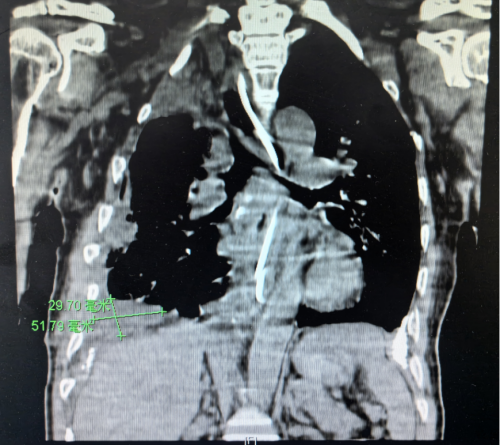

术后CT

针对患者高龄、手术高风险的实际情况,袁跃西及手术团队术前反复讨论、精准评估,制定了详细的手术策略。在排除手术禁忌后,袁跃西及手术团队为张根水在全麻下实施了开胸及胸腔镜辅助杂交手术。首先,在患者胸部切开一个20厘米左右的切口,并切除部分肋骨后进入胸腔。接下来,第一步“抽丝剥茧”分解致密的胸腔粘连;第二步清除脓胸及包裹性积液;第三步小心细致地剥离钙化的脓胸纤维板,尽量减少右肺的损伤;第四步借助胸腔镜,扩大手术视野,剥离胸顶部钙化的脓胸纤维板;第五步,修补破损的右肺,创面彻底止血,消毒胸腔,置入引流管,缝合切口。整台手术长达8小时,手术步骤严密有序,从患者胸腔内取出近5公斤脓渣和坚硬纤维板组织,令患者重获“呼吸自由”。术后,患者生命体征平稳,转入病房接受进一步治疗和护理。